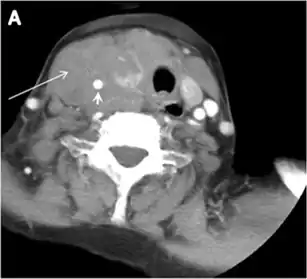

- Fig. 9. A 58-year-old male patient with persistence PTC at thyroid bed with hypervascular nodal metastasis. a–c Transverse greyscale and colour Doppler neck ultrasound demonstrate hypoehoic soft tissue in the left thyroid bed (white arrow in a). There are a heterogeneous enlarged lymph nodes at level 2 and 3 with markedly increased vascularity (white arrow in b and c). d–f Enhanced axial CT images of the neck demonstrate a 2.7 × 1.4 cm hypodense soft tissue lesion anterior to the left carotid sheath (white arrow). There are left-sided enhancing abnormal and enlarged lymph nodes at cervical level 2 and 3 (black arrows).[1]